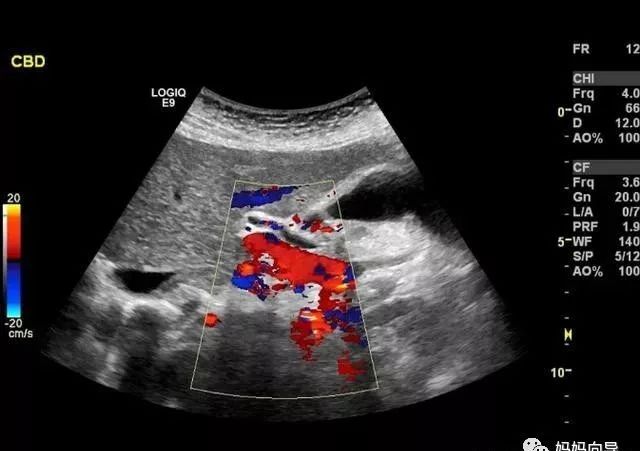

B超探测出来的头像是黑白的,只能探测到宝宝的大概情况,一般在孕早期做B超就够了。彩超探测出来的是彩色图片,可以探测到胎儿的血流情况,能够及时发现胎儿是否异常。四维彩超就像摄影机的VCR,能够及时发现胎儿先天性畸形。